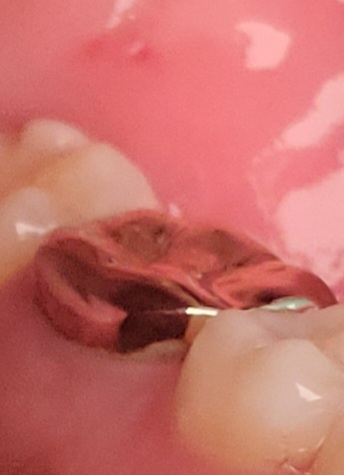

크라운 잇몸퇴축 많이 된 편인가요?

신경치료한 크라운인데요

다른 부분은 정말 미세한건 같은데 유독 저 부분만

하얀 부분이 잘 보이네요 통증같은 건 없는데

잇몸퇴축이 믾이 된 편인가요?

• 1번 째 사진

해당부위는 잇몸의 퇴축이라기 보다 보철물의 경계부위가 위로 형성되어 있어서 치아가 보이는것으로 보입니다.

경계부에 충치등이 생기기 않았다면 크게 문제를 발생기키지 않기 때문에 치실등으로 잘 관리를 해주는것이 좋습니다.

잇몸이 많이 내려간건 아니지만, 잇몸이 퇴축되서 치아가 노출되신거 같습니다. 크게 문제가 있는건 아니니 관리를 잘하시면서 사용하시면 될것같습니다.

심한 편은 아닌 것으로 보입니다. 앞으로 잇몸 관리 및 치실과 치간칫솔로 잘 관리해주셔야 합니다.